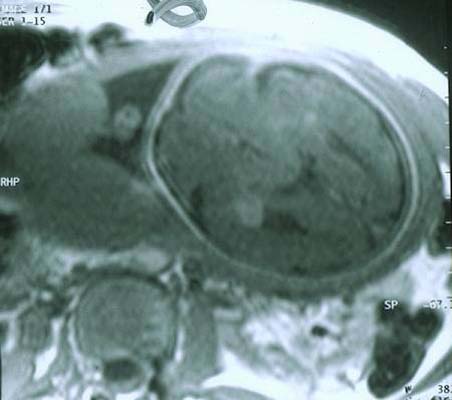

STB IRM